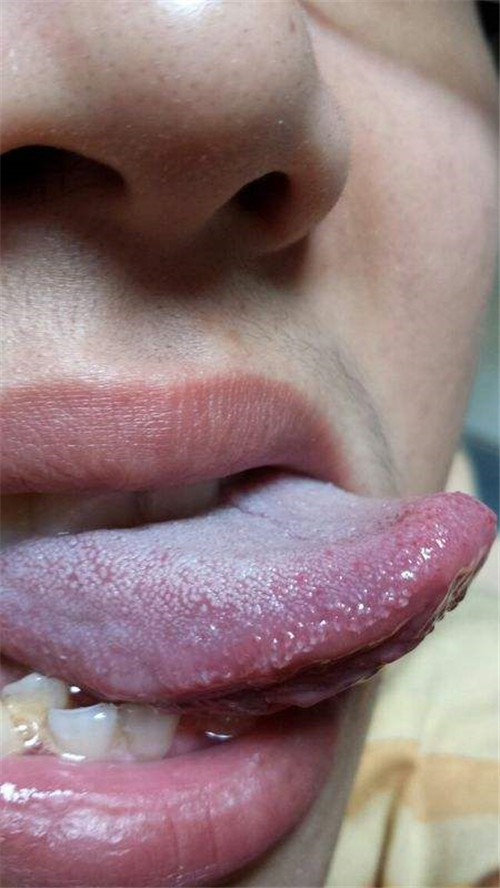

嘴唇白色念珠菌感染

舌頭白色念珠菌感染

口腔內白色念珠菌感染